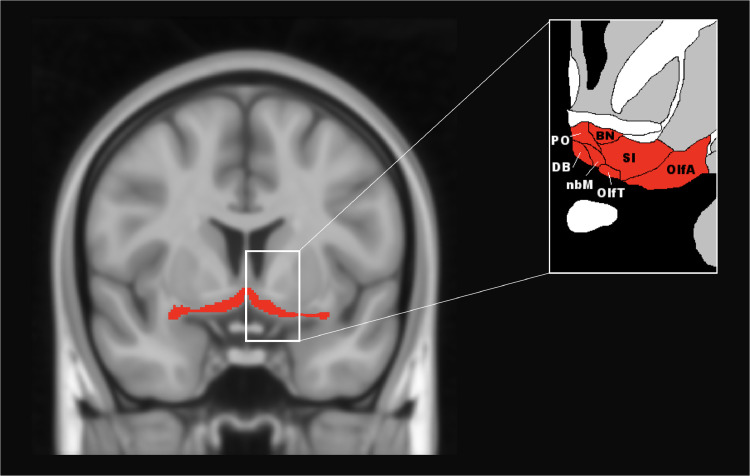

The basal forebrain is a subcortical structure located on the medio-ventral portion of the brain, ventral to the striatum (Fig. 1). It consists of a number of different structures, including the medial septal nucleus, the diagonal band of Broca, and the nucleus basalis of Meynert (ref. Mesulam, 2004a), with the major cholinergic pathways arising from these nuclei and innervating large portions of the neocortex and limbic system (ref. Zaborszky et al., 2015). Cholinergic activity linked to the basal forebrain has been shown to be crucial for several cognitive processes including attention (ref. Baxter and Chiba, 1999; ref. Bracco et al., 2014; ref. Muir et al., 1996) learning, and memory (ref. Sarter et al., 2003).